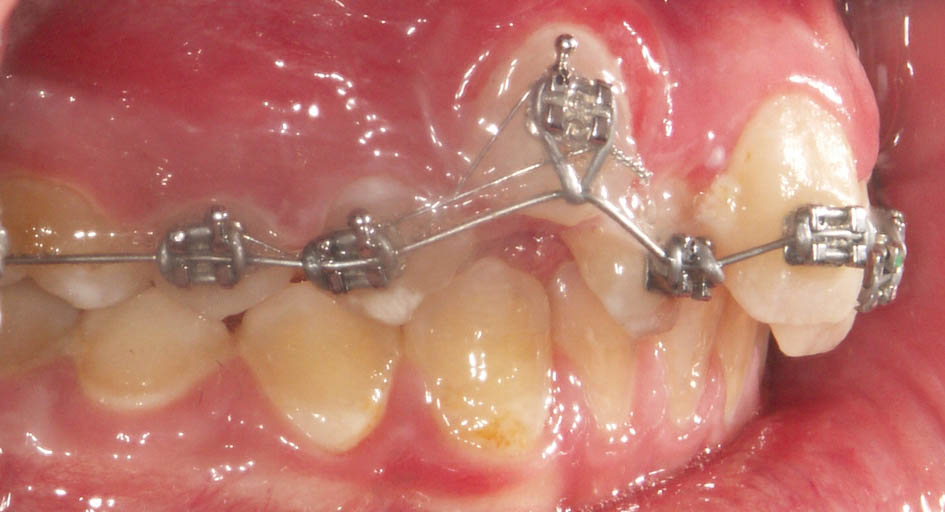

بعد از پروترودشدن قدامیها حالا میتوانید یک پلاک آندرسن (شکل 76-5 و 77-5) بسازید. میتوانید برای پلاک آرک لبیال نگذارید. در این مواقع مصرف پلاک تداخلی با داشتن براکتهای قدامی بالا ندارد و همزمان با مصرف این پلاک میتوانید سیم قدامیهای بالا را هم ضخیم کنید تا همزمان با رشد مندیبل، دندانهای بیمار هم مرتب شود.

شکل 76-5: پروترود شدن انسیزورها و ایجاد اورجت و تحویل پلاک آندرسن

شکل 77-5: پلاک آندرسن در حالت نوک به نوک برای بیمار ساخته میشود .